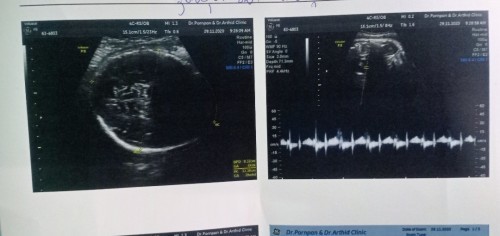

ในใบเขียน fm รึป่าวคะ ถ้าเขียน FM = female แปลว่า ผู้หญิง ค่ะ ถ้า m เฉยๆ m= male แปลว่า ผู้ชาย ค่ะ

ไม่มีภาพซาวน์หว่างขาค่ะ ดูไม่ได้ค่ะ

จะดูเพศน้องต้องดูรูปตรงหว่างขาคะ

ต้องดูภาพตรงหว่างขาค่ะ

ไม่เห็นเพศค่า